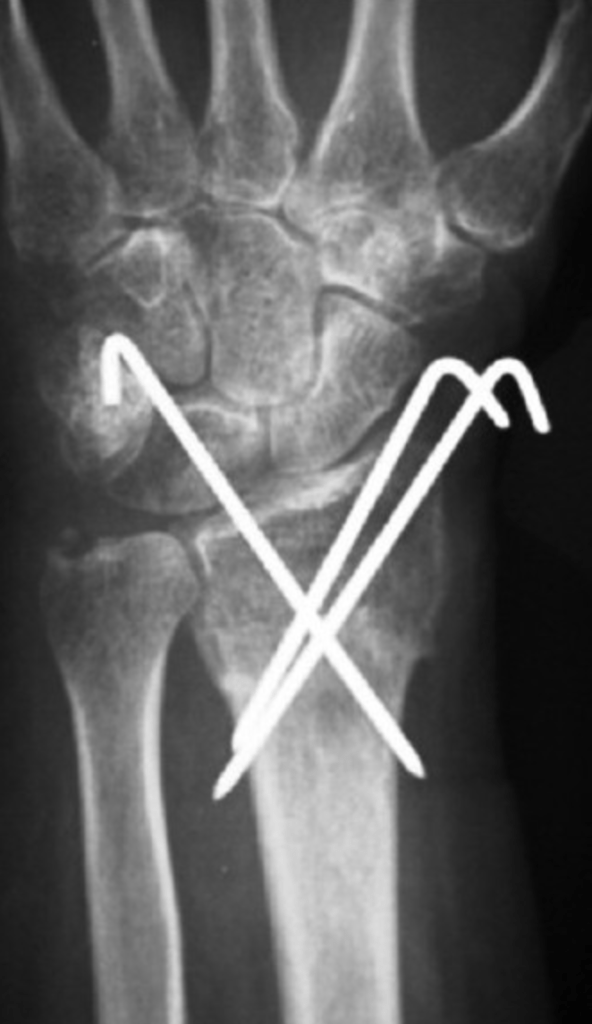

– An operation. At operation, the surgeon will again manipulate the bones back into position and fix them there with either some wires (these wires are a bit like barbeque skewers – they are relatively stiff with a pointed end to drill into the bone), or a plate. If a bone plate is used, a wound is made over the palm side of the wrist, and the plate inserted under the muscles and tendons.

…….And wires

Although surgery stabilises the bones and usually allows early movement, there are risks involved with surgery, and you can read more about these here. Although the surgeon will aim for a perfect position of the bones, this is not always achieved, and occasionally the fixation fails to hold the position of the bones. Late problems associated with the use of bone plates include tendon irritation or rupture, and the risks and benefits should be discussed with the surgeon before having this type of operation.